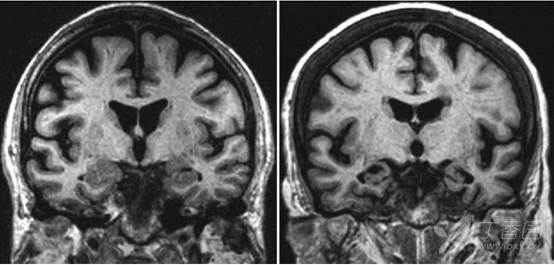

痴呆神经影像改变一 皮质萎缩之 阿尔茨海默病ad